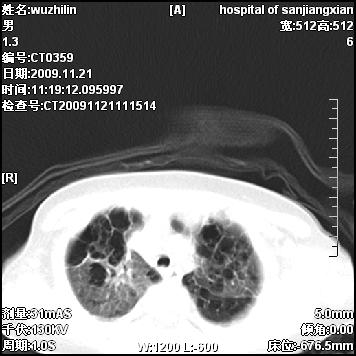

标题: PED3072: 1岁3个月患儿 胸部弥漫性病变 [打印本页]

标题: PED3072: 1岁3个月患儿 胸部弥漫性病变

弥漫性薄壁囊腔,胸膜下及肺底部占优势,双上肺磨玻璃密度影,首先考虑特发性肺间质纤维化,其次囊性肺纤维化,肺淋巴管平滑肌瘤病嗜酸性肉芽肿等;要结合临床综合考虑。

两肺布满多个薄壁含气囊腔,以下肺居多,伴磨玻璃样密度影,左侧气胸。两肺发育不全、两肺多发肺囊肿并感染,其次考虑肺囊腺瘤。